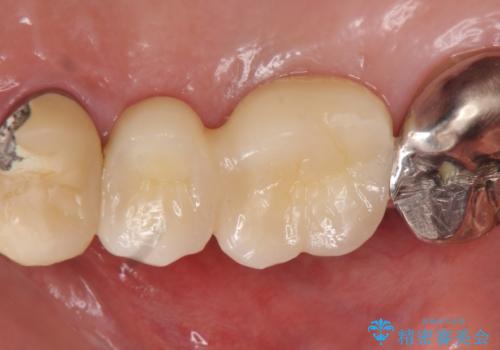

- 右上のブリッジでものを咬むと違和感があり、歯茎に膿の出口もできているので診て欲しいといらっしゃった方の症例です。

右上の567ブリッジを外したところ、右上5は歯根破折により保存不可能だったため、右上56部にインプラントを埋入し欠損補綴を行いました。

今回用いたオールセラミッククラウンはジルコニアフレームという白い素材の上にセラミックを盛っているため、審美性が非常に高いのが特徴です。

また、ジルコニアは人工ダイヤモンドの材料にも使われているほど高い強度を持っており、そのためオールセラミッククラウンは審美性だけでなく、奥歯やブリッジの補綴も可能とするクラウンです。